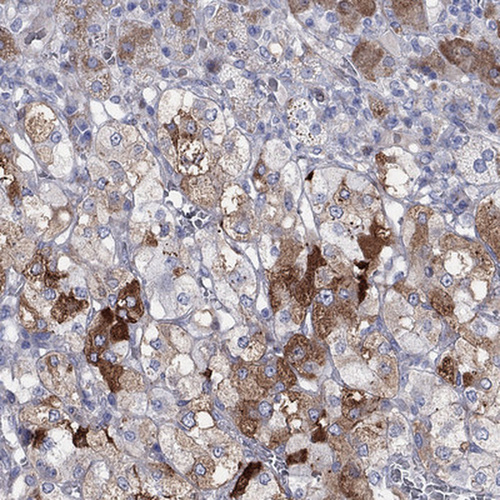

Immunohistochemical staining of human adrenal gland shows strong cytoplasmic positivity in medulla.